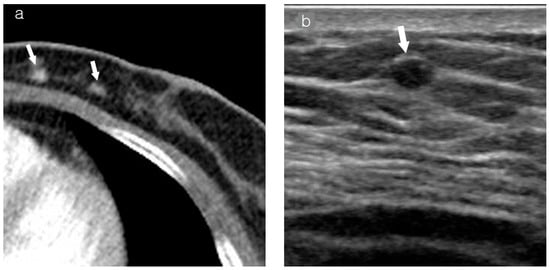

Table 2 summarizes imaging findings based on visibility. On mammography, a mass was observed in 73.8% (31/42) in the visible group, compared to 7.7% (2/26) in the non-visible group (p = 0.000). On MRI, a mass-type presentation was observed in 78.8% (41/52) in the visible group, compared to 38.9% (7/18) in the non-visible group (p = 0.002). Tumor background location on chest CT also significantly differed between the two groups. In the visible group, a fatty background was observed in 67.2% (39/58), compared to a glandular background observed in 16.7% (5/31) in the non-visible group (Figure 1 and Figure 2).

Figure 1.

Images of a patient who underwent left breast-conserving surgery 7 years ago. Recently, IDC was diagnosed in the left conserved breast. (a) Axial contrast-enhanced chest CT shows an enhancing lesion (arrows) in the inner central portion of the left breast. (b) On US, the mass (arrow) appears as a 0.5 cm oval hypoechoic mass located in a fatty background in the left breast. (c) CC view of mammography reveals an irregular hyperdense mass (arrow) corresponding to the lesion in the left breast. (d) The 2 min subtracted sequence of MRI shows an irregular heterogeneous enhancing lesion (arrows) corresponding to the lesion in the left conserved breast. IDC, invasive ductal carcinoma; CT, computed tomography; US, ultrasonography; CC, craniocaudal; MRI, magnetic resonance imaging.